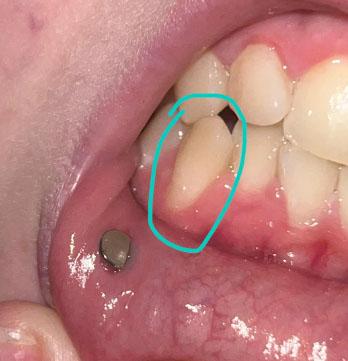

ocalized Gum Recession and Root Exposure on Lower Premolar – Full Dental Case Analysis (100% Zoom)

The circled tooth shows localized gum recession on a lower premolar, with visible root surface exposure. The gum margin has migrated downward, exposing the lighter-colored root area compared to the enamel above. The surrounding gum tissue appears mildly inflamed but without obvious pus or acute infection.

A metal stud visible on the lip is unrelated to the dental condition.

This presentation is consistent with early-to-moderate gingival recession, not active tooth decay.